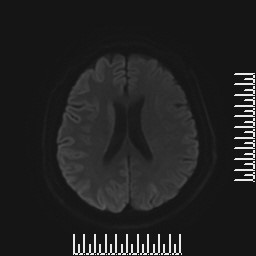

查体:问答及查体部分合作,反应迟钝,定向力定时力差,眼球运动检查,仅可向上及向右转动,四肢肌张力高,以右下肢为轻,可见左上肢不自主抖动,肌力检查、共济、感觉检查不配合。 辅助检查:颅脑DWI示右侧尾状核信号增高,双侧颞顶枕叶脑回样增高,脑电图提示背景节律无枕区优势,全导连续性双相或三相慢波发放,后头部为甚,睡眠周期性三相波少见,全导连续慢波活动,脑脊液常规、生化及培养未见明显异常,14-3-3蛋白阳性